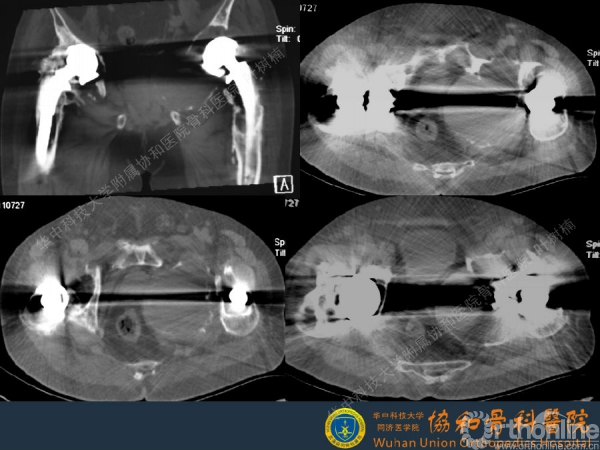

髋臼缺损的处理